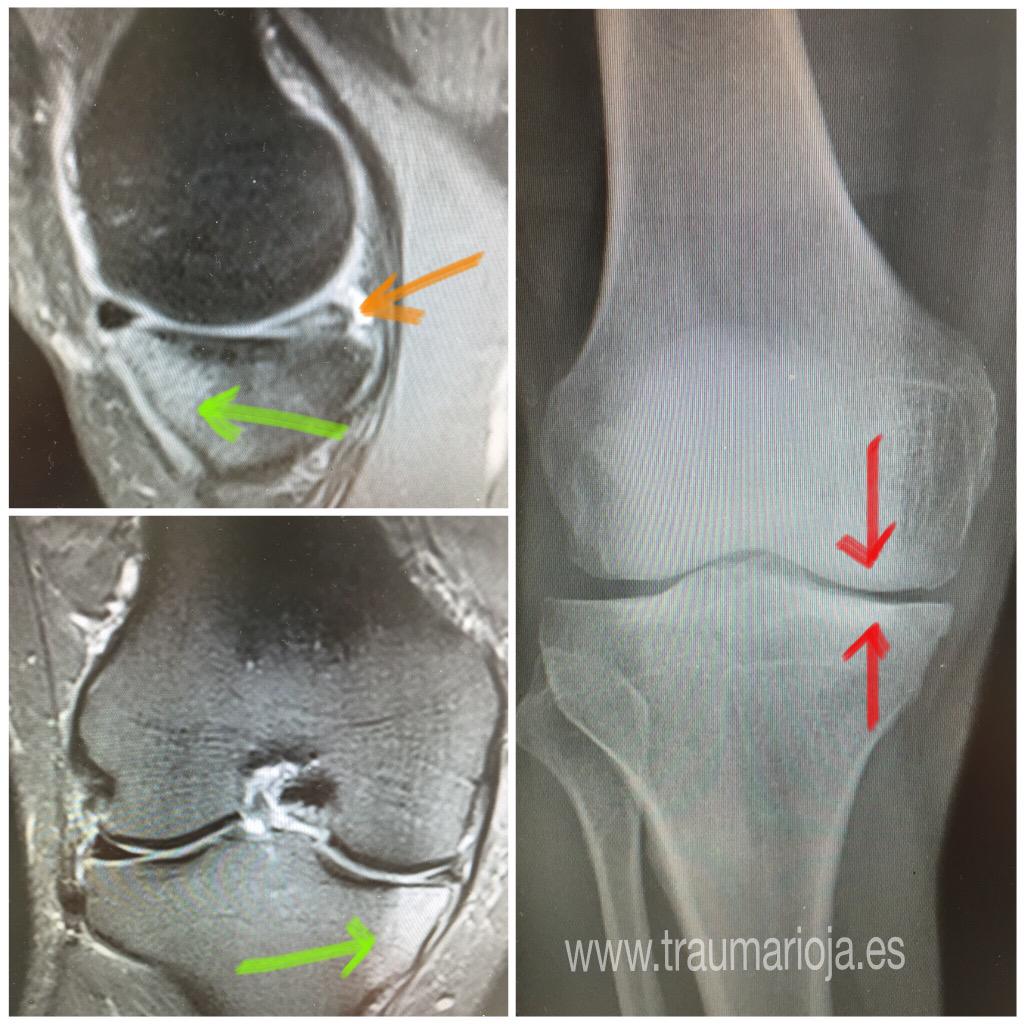

From twitter.com

Traumatología on Twitter "Artrosis compartimento interno. Pinzamiento Articular Edema Bone marrow edema is a buildup of fluid inside your bones. It’s typically the response to an injury or a condition like osteoarthritis. Bone marrow edema in the knee, also known as a bone marrow lesion, is a buildup of fluid in the spongy tissue in the center of. Joint effusion is where the fluids in the tissues around your. Articular Edema.

From www.researchgate.net

Typical MRI appearance of an osteochondral defect in the knee (a Articular Edema Or, it may be related to a health condition like osteoarthritis, a. Increasingly mris are used to evaluate joints of patients with arthritis. Bone marrow edema in the knee, also known as a bone marrow lesion, is a buildup of fluid in the spongy tissue in the center of. Joint effusion is where the fluids in the tissues around your. Articular Edema.